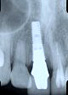

転倒時に強打し歯根から折れてしまった右の前歯を抜歯し、同時にインプラントを埋入してオールセラミッククラウンで治療しました。

X線で見るとインプラントの埋込がわかります。

期間/半年   インプラント費用/40万円